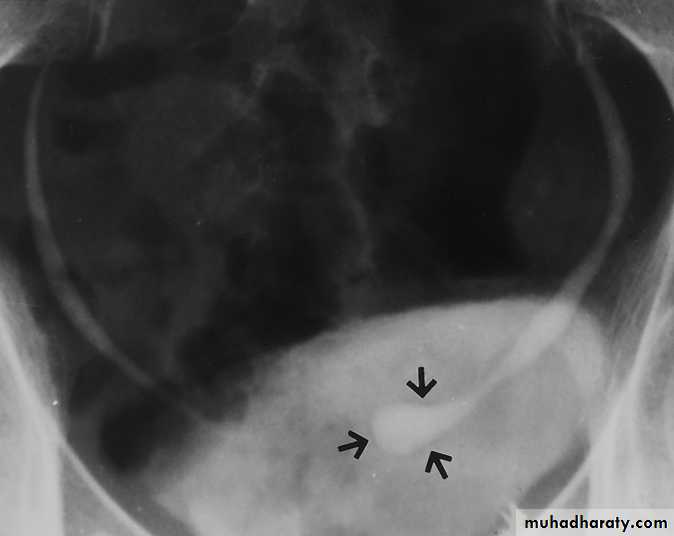

IVU :

- There is rounded or elliptical dilatation of lower end of ureter with thin lineal filling defect around it , resembling (cobra head appearance),

- Proximal dilatation of rest of ureter .

- In advanced cases hydronephrosis .

- In obstructed ureterocele , filling defect in the bladder